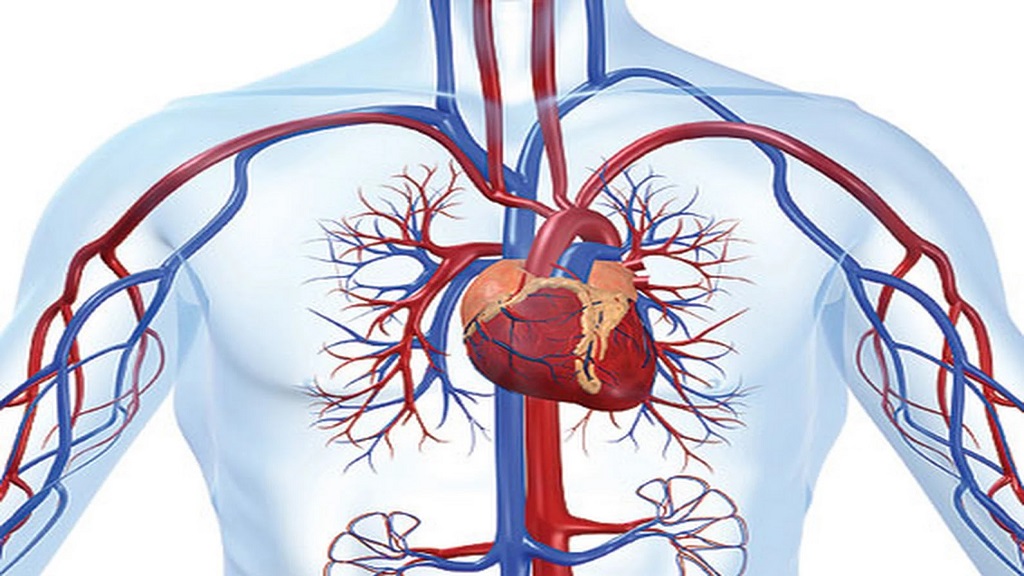

رؤيتك لصور شرايينك يحفزك على الاهتمام بصحتك

أشارت دراسة أجريت حديثا إلى أن الأشخاص الذين يرون صورا حية لشرايينهم المسدودة ربما يقبلون على اتباع نمط حياة صحي مقارنة بالمرضى الذين لا يشاهدون هذه الصور.

وخلال الدراسة الحالية حدد الباحثون بشكل عشوائي 3532 شخصا لديهم عامل خطر واحد على الأقل قد يسبب إصابتهم بأمراض القلب ولكن لا يعانون من أعراض تحتم اهتماما خاصا يتعلق مثلا بنمط الحياة أو تلقي علاجات ولا الحصول على صور لشرايينهم مع شرح ما فيها من إشارات على المشكلات الصحية التي تنتظرهم.

وكتب الباحثون في دورية لانسيت أنه بعد عام، قلت عوامل الإصابة بأمراض القلب لدى من شاهدوا صور أوعيتهم الدموية مقارنة بالمجموعة التي لم تشاهد مثل هذه الصور.

وبعد عام، تراجعت عوامل الخطر لدى من رأوا صور شرايينهم استنادا إلى مقياس شائع يعرف باسم مقياس (فرامنجهام) فيما زادت عوامل الخطر لدى المجموعة الأخرى.